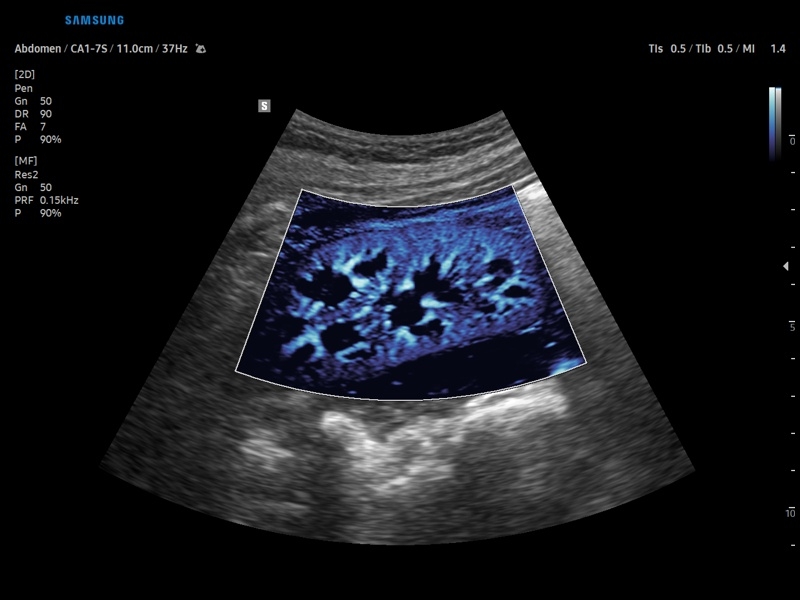

• Модуль CEUS+ (Contrast Enchansment UltraSound) - программа, позволяющая проводить обследование с применением контрастных агентов.

• Модуль MV-Flow – программа (режим), позволяющая визуализировать кровоток в микроциркуляторном русле с высоким разрешением без использования контраста.

• Абдоминальные исследования

• Сосуды брюшной полости:автоматическая, полуавтоматическая, ручная трассировка доплеровского спектра; ПСС, КДС, %СтПлощ, %Ст Диам, площадь сосуда, диаметр сосуда, объемный кровоток.